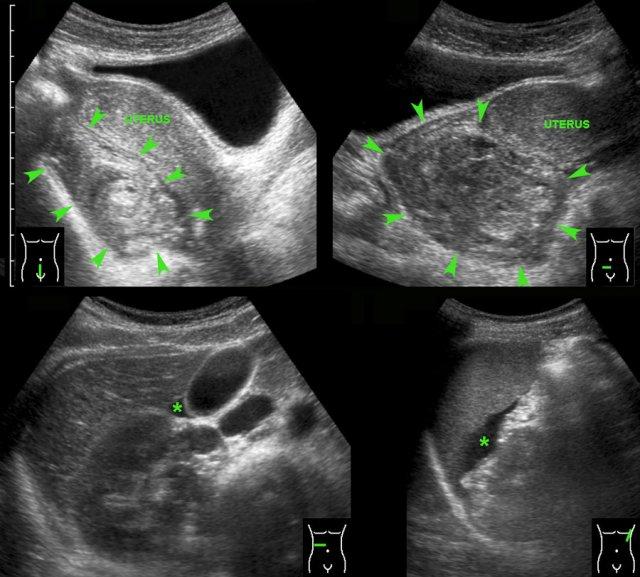

Các hình ảnh này của một phụ nữ 17 tuổi với cơn đau hố chậu phải cấp tính, dữ dội. CRP bằng 1.

Siêu âm phát hiện một nang buồng trứng phải thành dày, bờ không rõ và dịch tự do (*) trong túi cùng Douglas.

TVUS xác nhận hình ảnh dịch và một nang xẹp một phần, dễ ép xẹp ở buồng trứng phải.

Buồng trứng trái bình thường (hình dưới bên phải).

Cơn đau giảm dần và các xét nghiệm duy trì trong giới hạn bình thường.

Trong vòng một tuần, hình ảnh siêu âm hoàn toàn trở về bình thường.

Chẩn đoán có khả năng nhất: nang chức năng vỡ.